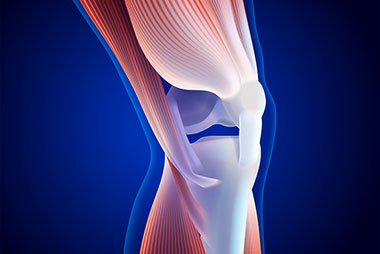

El trauma musculoesquelético ocurre cuando existe una transferencia de energía brusca hacia un segmento del cuerpo, lo que puede significar un daño en forma directa para todas las estructuras relacionadas. La lesión en una extremidad, aunque es frecuente en los pacientes traumatizados, en escasas ocasiones implica un riesgo vital inmediato. El traumatismo en la extremidad puede suponer un riesgo vital cuando provoca una hemorragia incontrolada, ya sea externa o interna. El riesgo de complicaciones, como insuficiencia renal, infecciones y/o gangrenas, se asocia generalmente a lesiones graves por aplastamiento de miembros.

Institución Badra y la Sociedad Argentina de Medicina de Urgencias y Emergencias (SAMUE) te invitan al taller de Trauma Musculoesquelético, dictado por Médicos Emergentólogos. El presente taller pretender brindar conocimientos en el manejo y abordaje inicial del paciente con trauma musculoesquelético. Puede depender la futura funcionalidad del lesionado, reconocer lesiones vasculares, nerviosas y/o síndromes compartimentales.

- Generalidades del sistema musculoesquelético.

- Anatomía y fisiología.